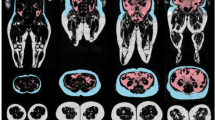

Pericardial fat, periaortic fat around the ascending aorta (AA), descending aorta (DA) and aortic arch, and abdominal subcutaneous and visceral fat were measured by MRI in older adults with (n=385, 69±8 years, 52% female) and without (n=50, 69±8 years, 58% female) risk factors for a CV event.

Individuals with CV risk factors exhibited greater fat volumes across all fat depots compared with those without risk factors. In analysis of covariance accounting for age, gender, race/ethnicity, diabetes, hypertension, coronary artery disease, smoking and body mass index (BMI), individuals with risk factors possessed higher epicardial, pericardial, AA, DA and abdominal visceral fat (P<0.05). When matched one-to-one on age, gender, race/ethnicity and BMI, AA and DA fat were higher in those with versus without CV risk factors (P<0.01).